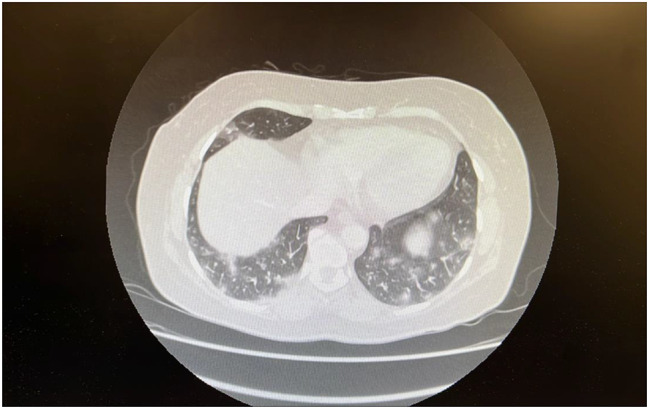

Anti-synthetase syndrome is a rare autoimmune disorder characterised by the presence of autoantibodies against aminoacyl transfer RNA synthetases. We report a unique case of a 54-year-old woman with anti-OJ anti-synthetase syndrome, characterised by the atypical occurrence of digital vasculitis in conjunction with the classic manifestations of anti-synthetase syndrome. Our patient presented with digital vasculitis affecting the right third and fourth fingers, rapidly evolving interstitial lung disease of the organising pneumonia subtype, sub-clinical myositis, arthritis and mechanic's hands. Notably, she had no prior history of Raynaud's phenomenon. Serological tests revealed positive anti-OJ antibodies and weakly positive anti-MI2 antibodies. Our patient's condition was managed with intravenous methylprednisolone then after stepped down to prednisolone and mycophenolate mofetil with successful therapeutic response.Current literature primarily highlights Raynaud's phenomenon and vasculopathy-related ischemia, whether occlusive or non-occlusive in anti-synthetase syndrome. This case study identifies digital vasculitis as a distinctive complication of anti-synthetase syndrome, anti-OJ subtype. It emphasises the importance of recognising vascular complications, including vasculitis, even when classic signs like Raynaud's phenomenon are absent. Further research is crucial to fully understand the range of vascular manifestations associated with anti-synthetase syndrome.